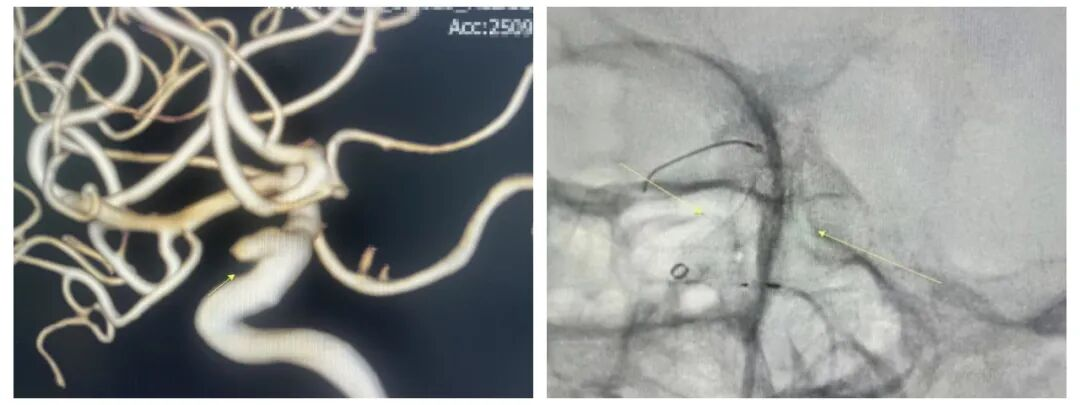

患者二:62岁女性,发现左侧颈内动脉C7段动脉瘤2年余,2年前因右侧颈内动脉C7段动脉瘤破裂出血在我院介入治疗术后,复诊。

▲患者左侧颈内动脉C7段动脉瘤,经弹簧圈填塞+密网支架植入术后,动脉瘤不显影